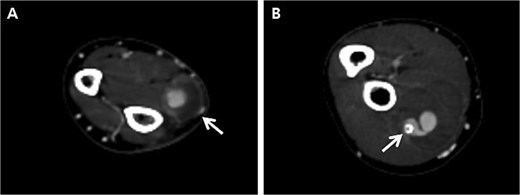

Initially, we conducted percutaneous endovascular exclusion of the proximal RAP using 3.5 × 26 mm Graftmaster covered stent (Abbott Vascular, Santa Clara, CA, USA) and observation of the distal RAP (Fig. 2). Nevertheless, no improvements were observed in the RAPs for 2 weeks after the procedure. A follow-up CT showed the distal migration of the covered stent and increased size of the RAPs. Distal lesion size increased from 0.8 cm to 1.5 cm (Fig. 3A) and the proximal lesion increased from 2.0 cm to 4.0 cm (Fig. 3B). At this point, surgery was considered suitable for the patient to achieve complete recovery.

Follow-up computed tomography of the right upper extremity, 2-weeks after the procedure. (A) Pseudoaneurysm at the distal radial artery, size increased from 0.8 cm to 1.5 cm (arrow); (B) Pseudoaneurysm at the proximal radial artery, size increased from 2.0 cm to 4.0 cm with distal migration of covered stent (arrow).